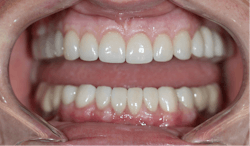

After the first phase consisting of caries control and periodontal treatment, the patient received soft- and hard-tissue crown lengthening by laser (figure 5). After an eight-week healing period, full-mouth cosmetic restorations were placed, which included full- and three-quarter-coverage e.max crowns and zirconia bridges (figures 6–7).

Following therapy, the patient was seen every three months for hygiene recare and to evaluate the status of caries and gingival inflammation. CariFree CTx4 Gel, home-administered sodium fluoride trays, and interproximal irrigators were given to the patient to increase resistance to caries. Oral hygiene instruction was an integral part of the recare visits and proved to be valuable in maintaining the patient’s results two-and-a-half years later (figure 8).